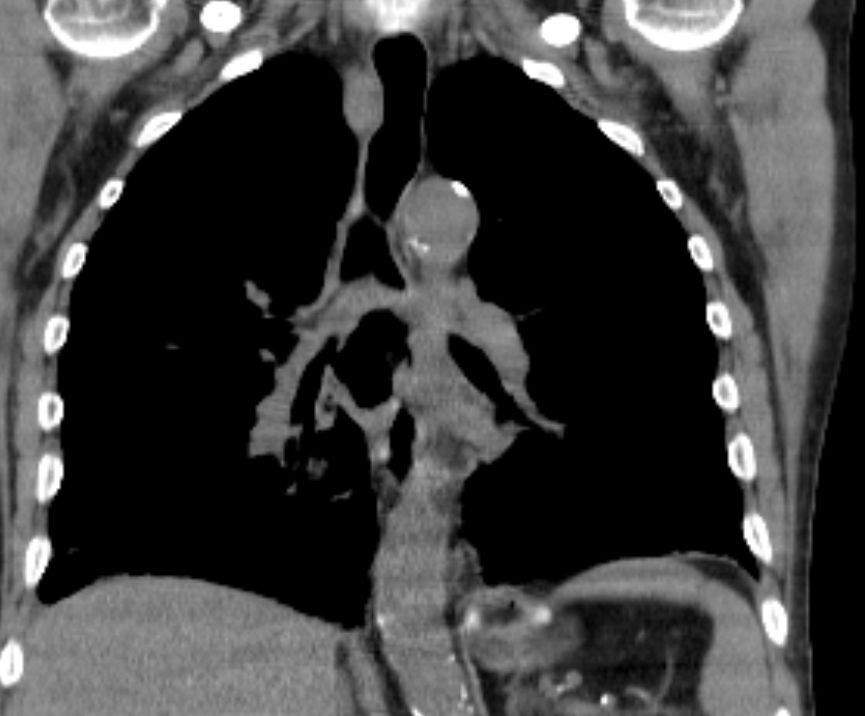

Primär zerebral metastasiertes Adenokarzinom des rechten Unterlappens. Im CT Tumor kavernenartig zerfallend. Jetzt: Sero-Pneu.

Sero-Pneu im CT